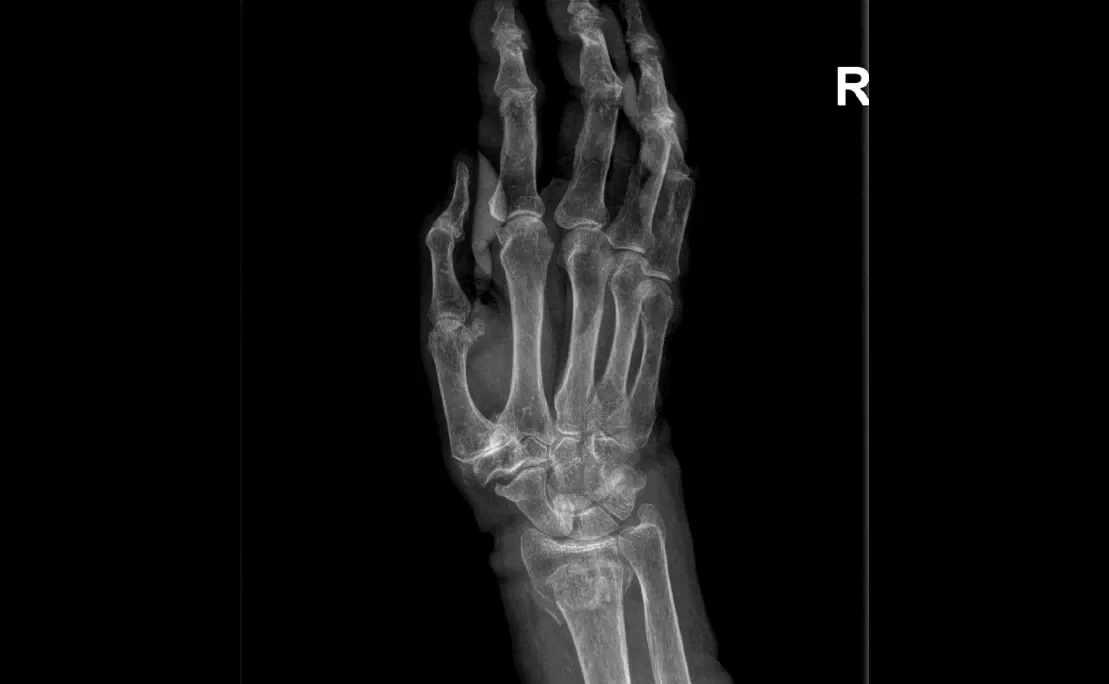

Polsartrose & Pisiformetriquetrale artrose

Wat is het?

Polsartrose is slijtage van het kraakbeen in één of meerdere polsgewrichten. Dit kan ontstaan in het:

- Radiocarpale gewricht (hand–pols)

- Midcarpale gewrichten

- Pisiforme–triquetrum gewricht

- DRUJ (spaakbeen–ellepijp)

Oorzaken zijn vaak: doorgemaakte breuken of ligamentletsels, doorgemaakte infectie, reumatische aandoeningen.

- Scaphoidectomie + four-corner fusieHet scaphoid wordt verwijderd, vier polsbeentjes worden vastgezetOngeveer 45% beweeglijkheid en 80% kracht blijft behouden

- Proximale rij carpectomieVerwijderen van scaphoid, lunatum en triquetrumNieuwe scharnierfunctie tussen capitatum en onderarmResultaten vergelijkbaar met four-corner fusieSoms aangevuld met een resurfacing-prothese